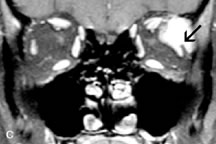

Breast carcinoma metastatic to the orbit has been demonstrated to be hypointense to the surrounding orbital fat on T1-weighted studies and hyperintense on T2-weighted images and has an affinity to the extraocular muscles (Fig. 20).50,64 The MRI characteristics of prostate carcinoma metastatic to the orbit have been described as involving the greater and lesser wing of the sphenoid, orbital roof, and optic canal. Diffuse bone hypertrophy with isointense or slightly hyperintense tissue on T1-weighted images represents the osteoblastic carcinomatous bone infiltration. Contrast enhancement is variable on T1-weighted and fat-suppressed images.65

Fig. 20. A. T1-weighted MR scan demonstrates nodular enlargement of both medial rectus muscles (arrows). B. T1-weighted fat-suppressed contrast-enhanced scan confirms the presence of small metnstatic deposits within the muscles (open arrows).